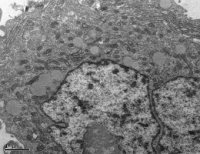

⑥透射电镜、外泌体粒径检测:鉴定药物是否装载,但效率不能用该方法评估。

外泌体(Exosomes)作为当前科研界的热度话题,很多人觉得它很神秘,不知道它在疾病治疗或发生、发展中扮演什么样的角色,今天我们跟大家一起基于文献来探讨一下外泌体具有的功能。 先回顾一下外泌体的基础知识。外泌体是细胞分泌到胞外的一种囊泡(Extracellular Vesicles,EVs),其大小为 30-150 nm,具有双层膜结构和茶托状形态,含有丰富的内含物(包括核酸、蛋白和脂质等),参与细胞间的分子传递。 所有的细胞都能分泌外泌体,但是不同细胞分泌的外泌体不管在数量